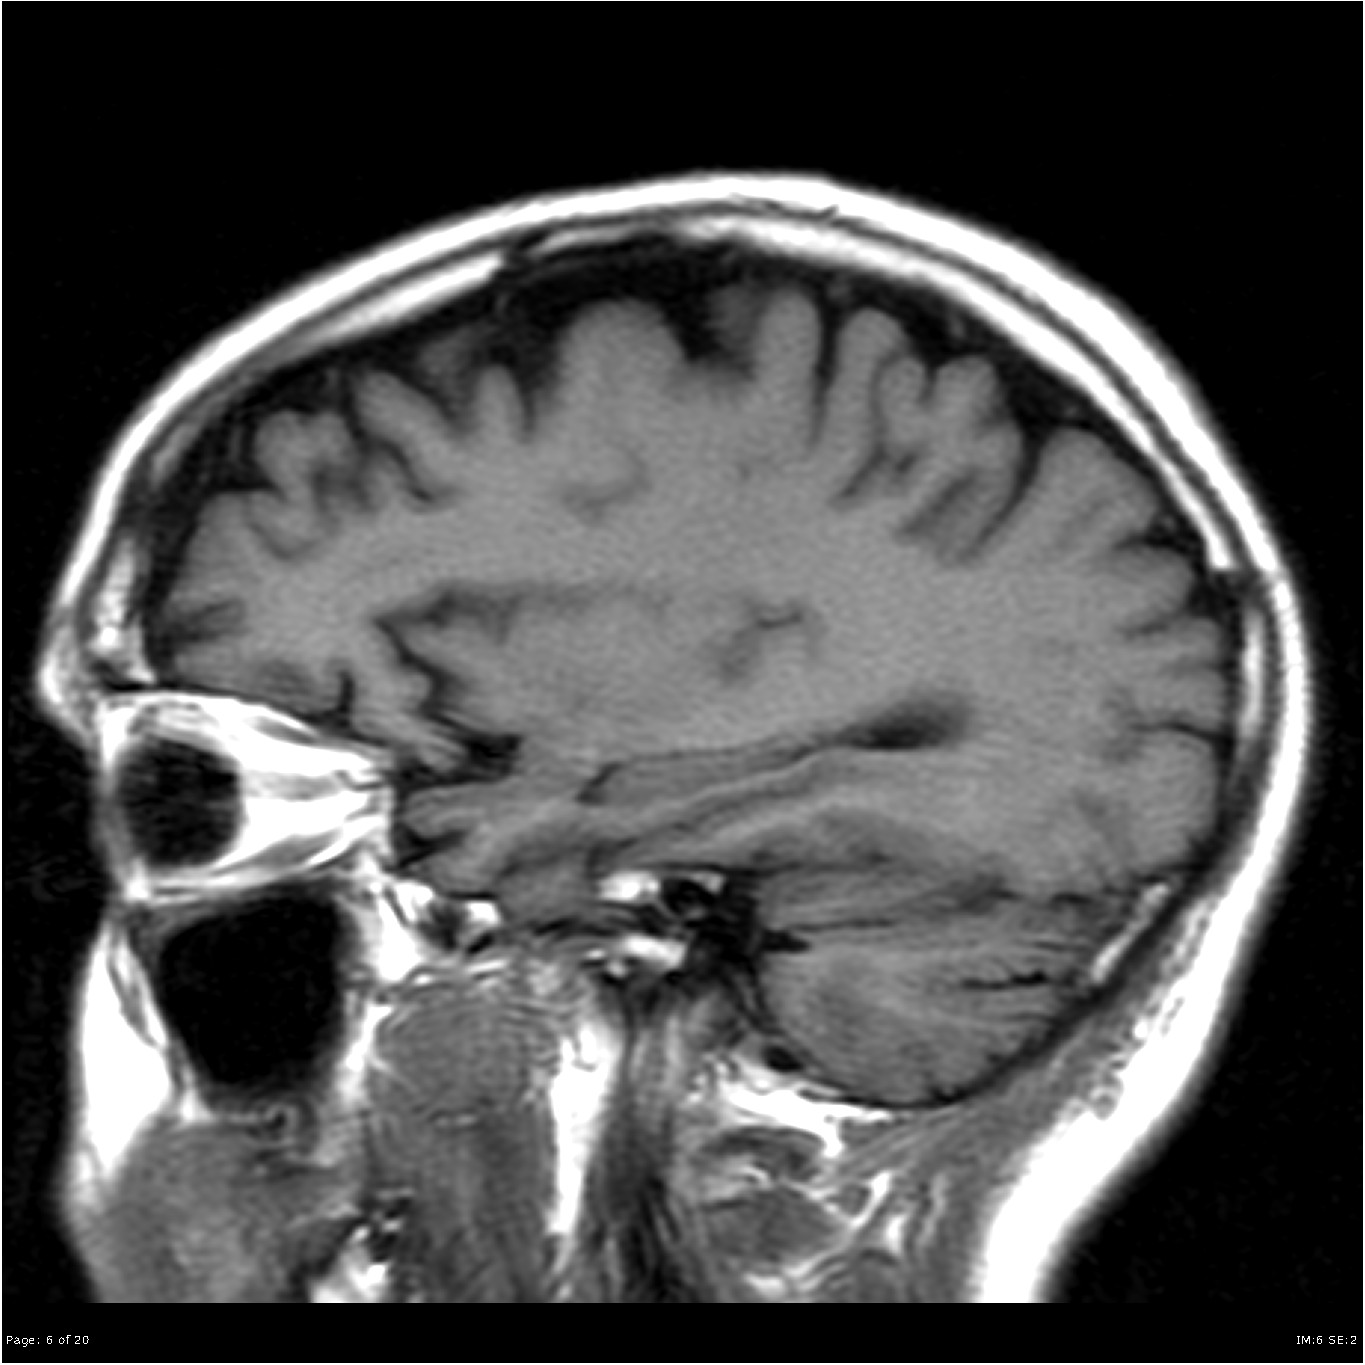

Brain MRI And Dementia Stock Image. Image Of Brain, Sagittal - 105374245

www.dreamstime.com

www.dreamstime.com

mri dementia failure dieting predict loss miethke hydrocephalus sagittal behandlung